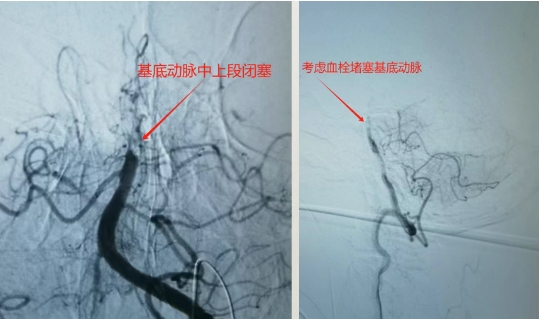

56岁的沙先生,是一名远洋渔船作业人员,工友发现意识不清10余小时。既往甲亢,房颤病史。入院查体深昏迷,刺痛无反应,四肢无活动,双侧病理征阳性,头颅CT提示未见脑内出血。入院诊断:急性基底动脉闭塞,脑干梗塞,房颤。实施术式:脑血管造影,基底动脉机械取栓,脑动脉导管溶栓手术�术中造影可见基底动脉闭塞,考虑血栓脱落导致。不及时开通,致死的可能性大�进一步采取支架及取栓导管抽吸取栓,微导管动脉内溶栓手术方式,及时开通了基底动脉主干及主要分支�患者术后刺痛反应较前改善,浅昏迷。经气管切开,脱水,改善脑循环等积极治疗后,病情稳定后转回当地樱花动�